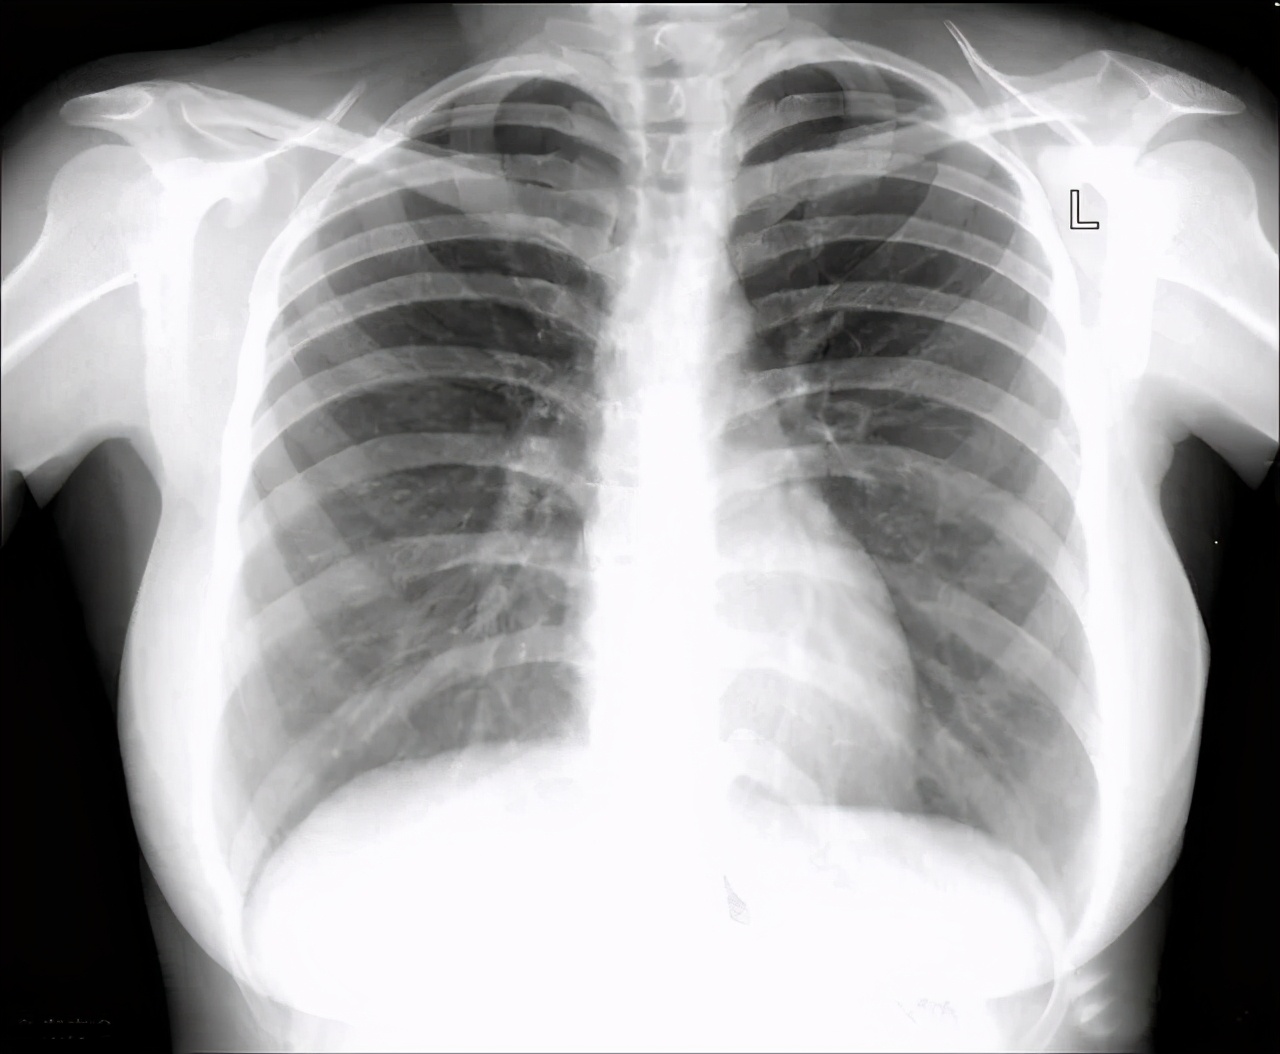

肺纹理是指从肺门向外呈现放射状分布的树枝状影。我们的肺部有很多动脉、静脉,在拍片的时候可以看到胸片上有很多像树枝一样的 经脉 ,随着逐级分支,纹理逐渐变细。

而胸片上的肺纹理就是指肺的细支气管、血管、淋巴管等等。当这些气管、血管增大时,就会显示一个肺纹理增粗。